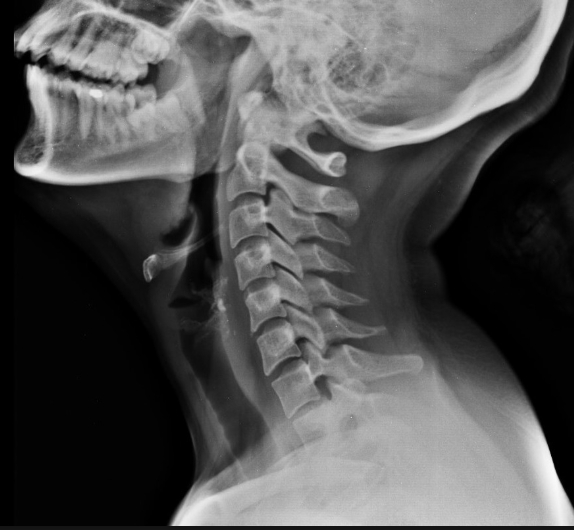

Trzydniowy kurs FDM Cranio opiera się na technikach i modelu FDM oraz jego wykorzystaniu w regionie mózgoczaszki, twarzoczaszki oraz kręgów szczytowych. W trakcie kursu uczestnicy zostaną zaznajomieni z anatomią twarz-, i mózgoczaszki, palpacją szwów i ważniejszych struktur nerwowo-naczyniowych oraz mięśniowo-stawowych, jak również omówione zostaną zadania i funkcje układu autonomicznego.

- anatomia nerwowo-naczyniowa regiony podpotylicy i szyi

- niestabilność kręgów szczytowych a linia Mc Rae, Mc Gregora i Chamberlaina, etc.